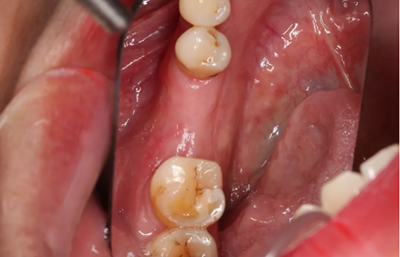

9、術(shù)后六月復(fù)診,種植前

軟硬組織愈合良好并上皮化,牙槽嵴形態(tài)保存較好。缺牙間隙:12mm,合齦距:7mm。

(攝于2017年2月15日)